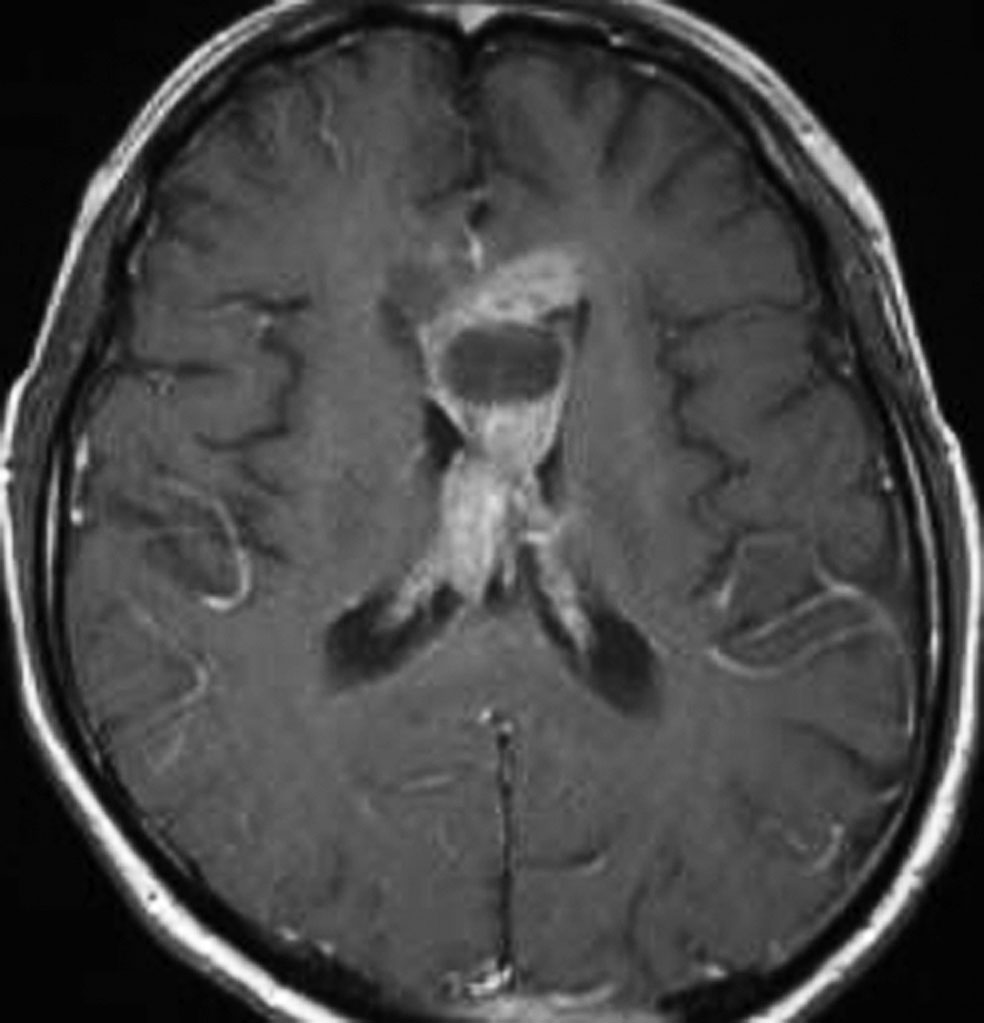

20歳くらいから尿崩症があり,2年後に汎下垂体機能低下症と軽度の認知機能低下を生じました。脳室壁と松果体,神経下垂体にジャーミノーマが広がっているのですが,脊髄背面と脳幹部の周囲にも腫瘍結節が見られました。脳室上衣以外の部位に腫瘍があるので,播種を疑いました。ジャーミノーマの播種というのは実際にはとても珍しくてなかなかみないものです。HCGは軽度の上昇,鼻孔から下垂体部分を生検して病理確定診断して,化学療法と脳脊髄照射 25.2Gy をしました。腫瘍は1コース目の化学療法でほとんど消失したので,他の組織型の悪性混合性胚細胞腫瘍ではないと考えられます。

3年後に脳室壁に再発しました。脳梁と脳弓の機能低下があり認知機能低下は高度でした。松果体と神経下垂体には再発はありません。